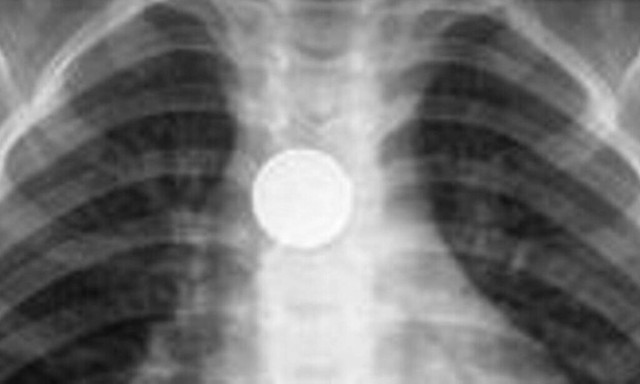

Όπως εξηγεί παιδίατρος, συνηθέστερα αντικείμενα που καταπίνουν τα παιδιά, ηλικίας από 6 μηνών έως 4 ετών είναι νομίσματα, μπαταρίες, κουμπιά, παιχνίδια και μαγνήτες, τα οποία αν βρεθούν στον οισοφάγο ή στο στομάχι χρειάζονται άμεση εξαγωγή.